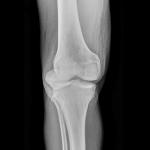

514

Abordaje anterolateral con osteotomía del epicóndilo en fracturas de platillo tibial. Resultados funcional y radiológico a los 6 meses de seguimiento

Víctor A. Ciccarello, Isaac Aranibar, Martín E. Romagnoli, Gonzalo J. Blanco O´Dena, David Espinoza Mendoza

530

Fracturas de platillo tibial tipo II-III de Schatzker tratadas con aloinjerto óseo impactado o técnica de rafting. ¿Es necesario llenar el vacío? Estudio de cohortes comparativo en 80 pacientes

Sebastián Pereira, Germán Garabano, Andrés Juri, Leonel Pérez Alamino, Joaquín Rodríguez, César Á. Pesciallo, Fernando Bidolegui